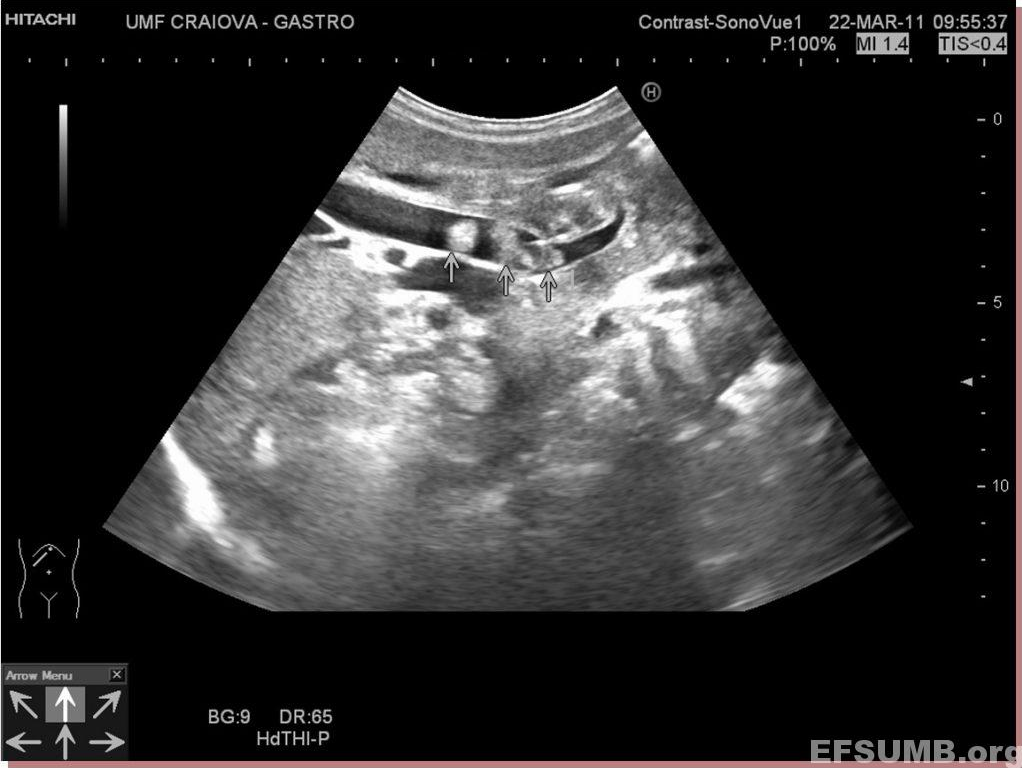

Standard ultrasound shows multiple echogenic rounded images, without shadowing and a dilated common bile duct.